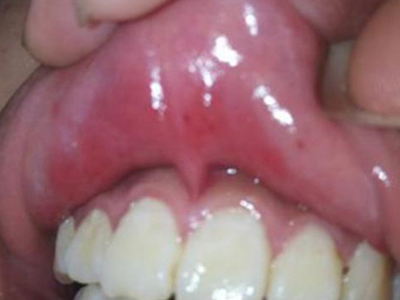

口腔溃疡又称复发性口疮,是慢性的口腔黏膜小溃疡,深浅不等,为圆形或椭圆形损害,可反复和周期性复发。多发生于口腔非角化区,如唇黏膜、舌头等处,预后较好,可自行痊愈。

口腔溃疡为圆形或椭圆形,直径0.2-0.5cm,溃疡单个或由数个连成一片,溃疡表浅边缘整齐,外观呈灰黄色或灰白色,上覆盖黄白渗出膜,周围黏膜充血、水肿而有红晕。

皮损局部有烧灼样疼痛,于进餐时加重,影响进食、说话。严重溃疡直径可达1-3cm,深及黏膜下层甚至肌肉。